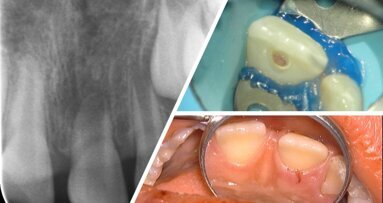

Die facings komen vooral voor in het front. Zijn de frontelementen het belangrijkst binnen de esthetische tandheelkunde?

Beekmans: We willen niet alleen maar bezig zijn met de frontelementen. Veel mensen komen bij ons omdat een voortand afbreekt, maar vaak zitten de problemen achter in de mond en komen die later tot uiting in het front. We moeten dan bijvoorbeeld eerst kijken hoe we de beet kunnen verbeteren of herstellen.

Beekmans: Dat is bijvoorbeeld de trend align-bleach-bond, waar het oplijnen van tanden met behulp van aligners een onderdeel van is. Als je tanden op de juiste plek zet, ze wat witter maakt en ze mooi maakt door – met behulp van ets-bonding – kleine randjes composiet te bouwen, krijg je een duurzaam resultaat. Vroeger werd er veel aan tanden geslepen, met alle gevolgen van dien.